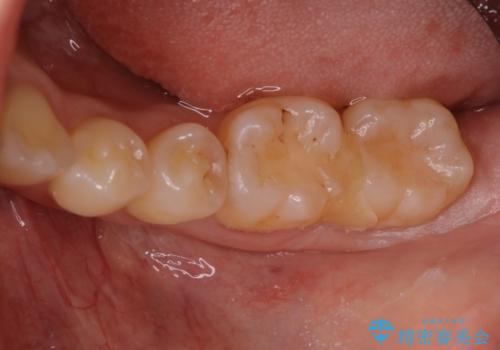

他院で虫歯と言われた。

- 他院で虫歯と言われたが、銀歯は患者様自身嫌だということでインターネットで当院のサイトを見ていただき来院されました。

カウンセリングを進めていったところ、やはり銀歯は嫌だという話になりセラミックでの治療になりました。